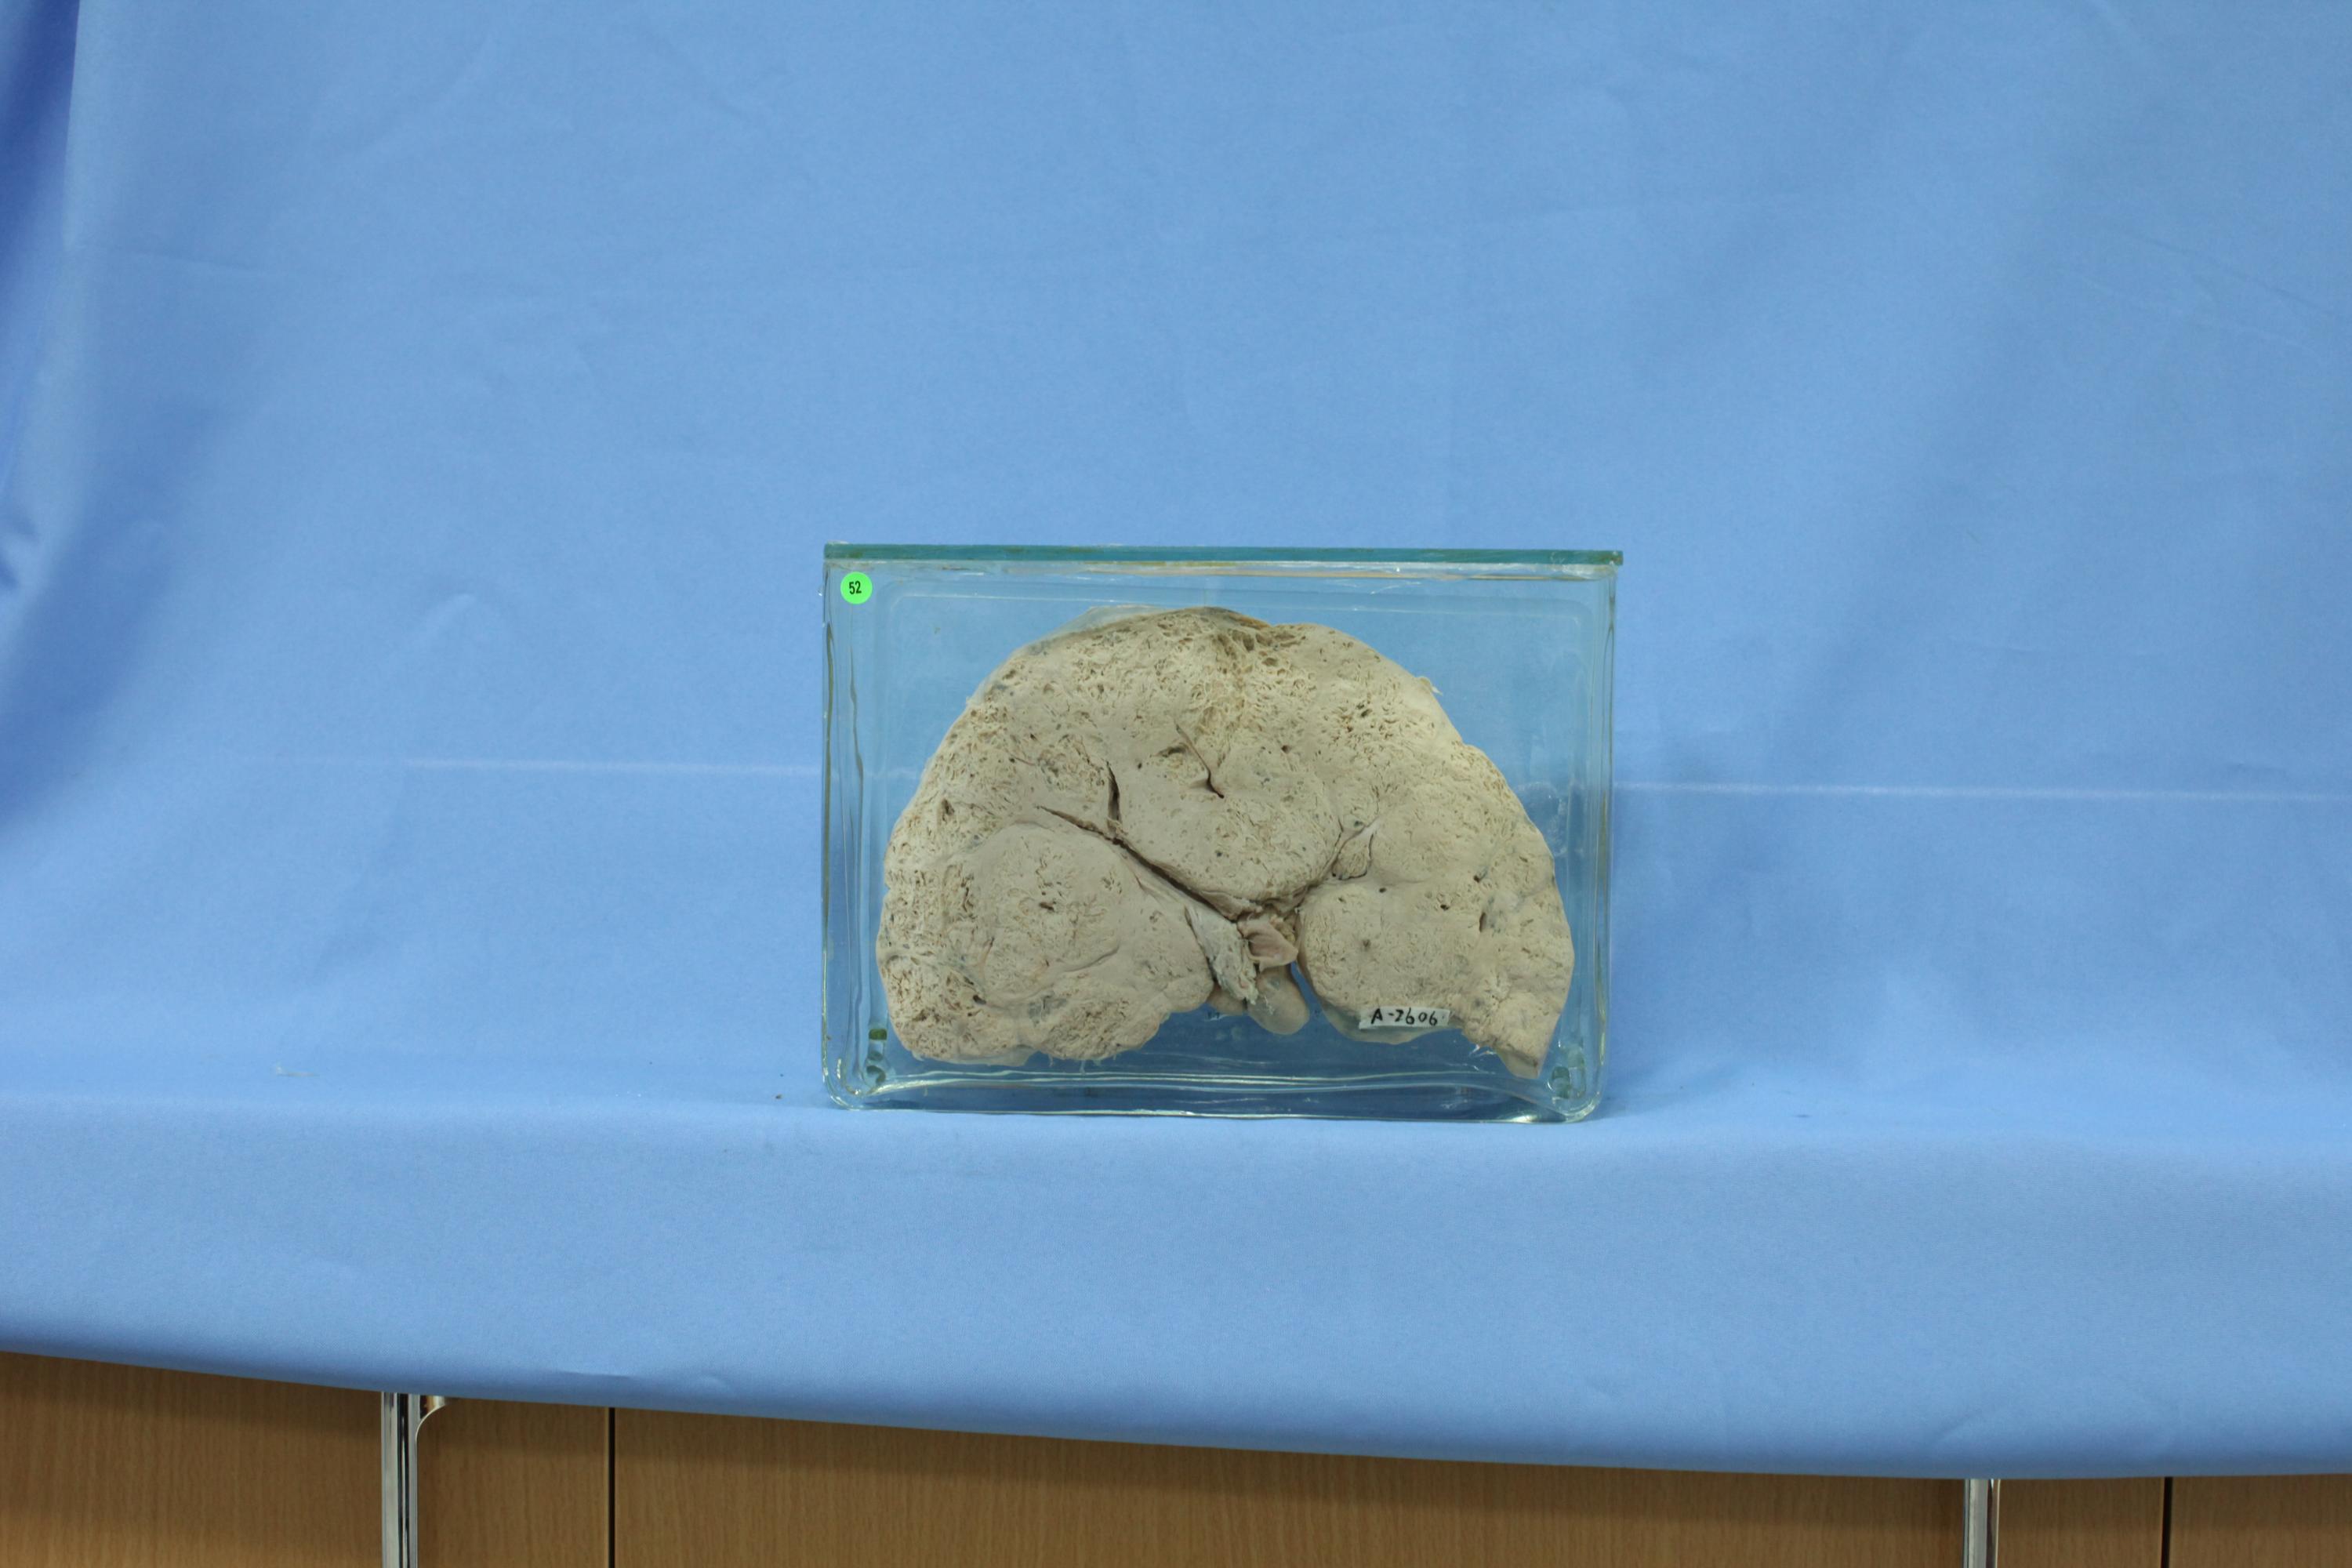

肝脏疾病-14- 52 肝转移性胃癌 (解剖号:A2606)

女,45岁。主诉“上腹部坚硬块状物逐渐增大,并疼痛1月余”。解剖诊断“胃幽门部腺癌,累及浆膜层,经淋巴及血道广泛转移”。肝脏体积增大,大部分被灰白色癌组织侵犯,癌组织疏松,易脱落。